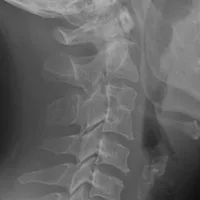

RX lateral de cuello donde observamos fusión de c3 con c4.

Seleccione el tipo de anomalia vertebral:

Sindrome de Klippel feil